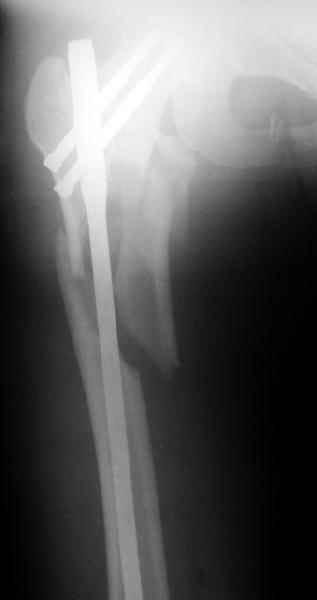

Другое наблюдение:Мужчина, 1957 г.р. Травма в результате ДТП 12.09.04г.

Диагноз: Закрытый оскольчатый подвертельный перелом правой бедренной кости со смещением отломков, оскольчатый перелом большого вертела, отрывной перелом малого вертела.Сопутствующие заболевания: Язвенная болезнь желудка, ремиссия.

Наверно, можно и так сказать, но можно и тоже самое - 4-фрагментный вертельный перелом. Выбор тот же, но с учетом молодого возраста реконструкционный гвоздь тут более применим. Вот уже наш пример.

Перелом подвертельный. Лечение оперативное, срочное,

PFN с длинной ножкой чтобы избежать стрессовые изменения в будущем. Обычно у молодых людей требуется проводить рассверливание канала как при гвоздевании.

полную нагрузку через 6 недель т.е. после образования костной мозоли, что позволить более или менее сохранить длину шейки.